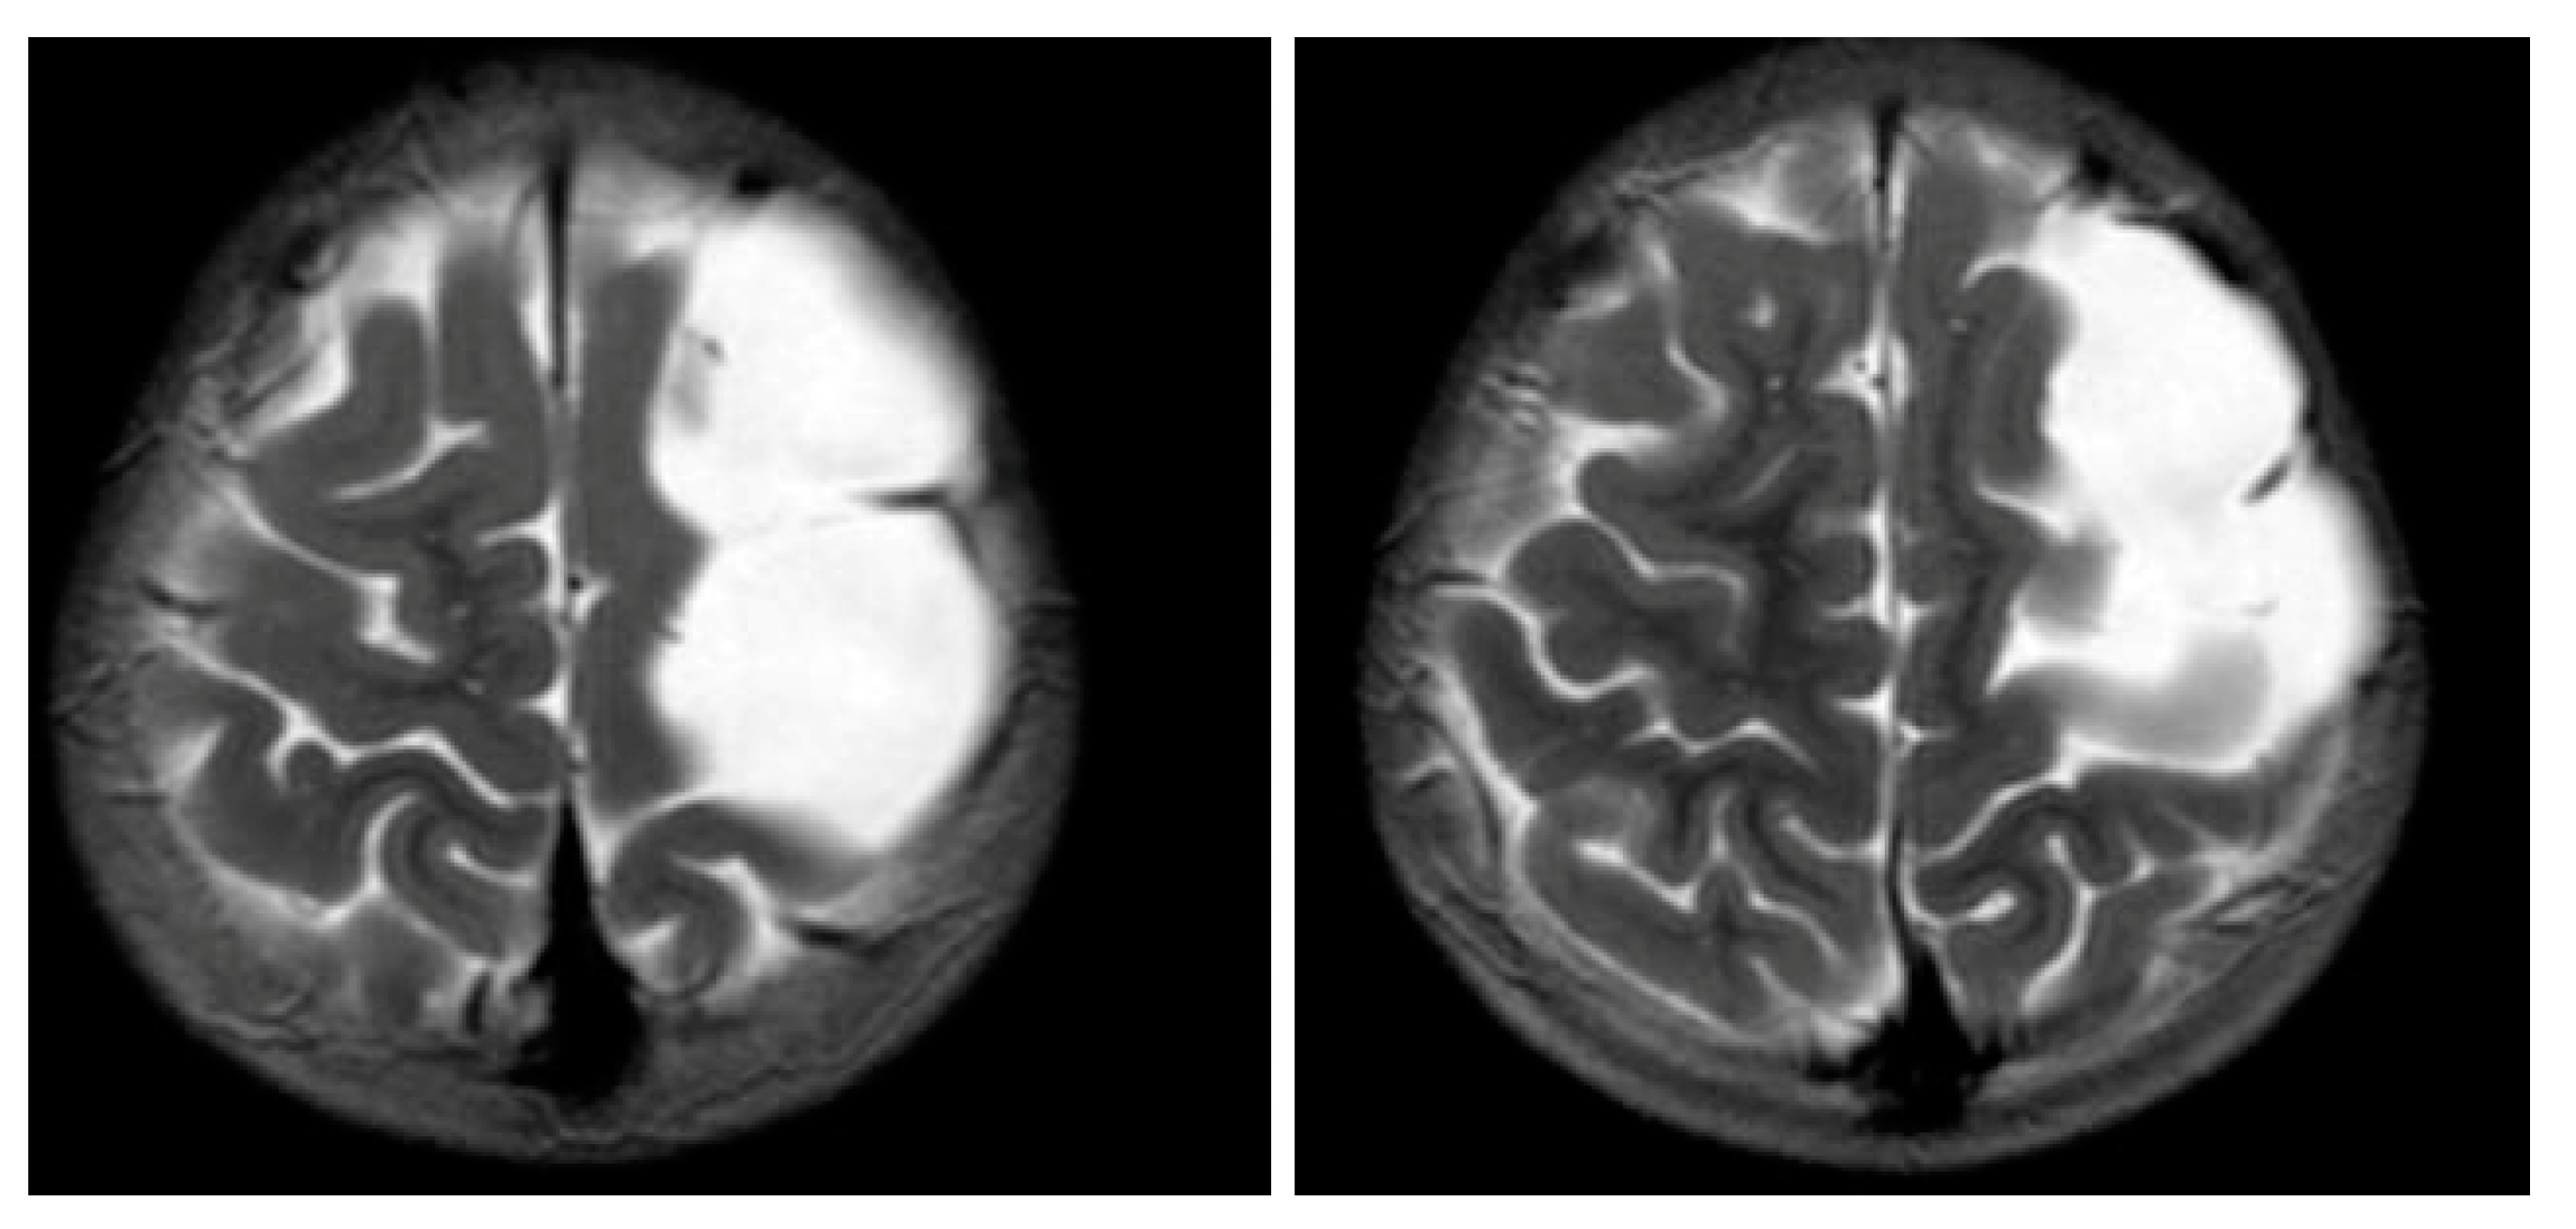

Figure 1 and Figure 2 reveal a change in signal of arachnoid cyst suggestive of interval hemorrhage with a thin subdural hematoma along its inferior aspect. Minimal edema in the subjacent Rolandic cortex was present. Given the patient’s stroke-like presentation, an MRA of head and neck was administered, which was found to be normal. The findings, with a comparison of the previous MRI of the patient at age 4 (Figure 3 and Figure 4), are consistent with a ruptured arachnoid cyst. No acute neurosurgical intervention was performed due to the absence of raised intracranial pressure and reduction of neurological symptoms. A routine EEG performed in the emergency department exhibited interictal epileptiform discharges over the left and right central–temporal region during drowsy and sleep states, suggestive of increased risk for partial seizures from these regions.

Figure 2. MRI T2WI, axial section in 2019. A very thin subdural hematoma is identified along the left convexity with mild edema noted in the subjacent perirolandic cortex. Decreased T2 signal is now identified within the cyst when compared to Figure 3 and Figure 4, which is suggestive of interval hemorrhage. These findings are consistent with a ruptured arachnoid cyst.

Figure 4. MRI T2WI, axial section in 2012. An extra-axial, well defined CSF structure lesion is identified in the left vertex with the following measurements: anteroposterior, 64 mm; oblique craniocaudal, 53 mm; transverse dimensions, 23 mm. This lesion causes a moderate compression effect of the underlying frontal and parietal gyri at the vertex with scalloping of the inner table. These findings are consistent with a moderate-sized arachnoid cyst at the left frontoparietal vertex.